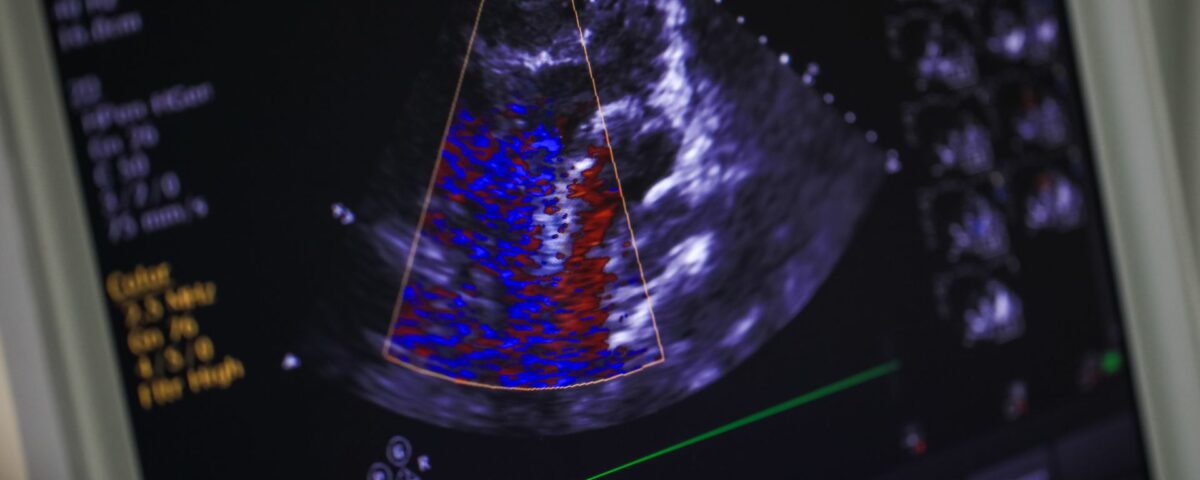

An echocardiogram is a standard diagnostic tool in cardiology used to assess the heart’s structure and function. It provides detailed images that help physicians identify various cardiac conditions. Understanding this procedure can provide clarity for patients undergoing cardiac evaluation. Here is more information on what an echocardiogram is, how it functions, and the types of problems it can detect:

An echocardiogram is a non-invasive test that uses sound waves to produce live images of your heart, so doctors can see how it is beating and pumping blood. The images show the size and shape of the heart, along with its chambers and valves. Doctors use this test to diagnose and monitor certain heart conditions by checking the heart’s chambers and valves, allowing them to evaluate the heart’s overall function. The information gathered helps in creating a personalized treatment plan.

The procedure uses ultrasound, which emits high-frequency sound waves. A device called a transducer sends sound waves through your chest toward your heart, and these waves bounce off the heart’s structures. The transducer then picks up the returning echoes, which a computer converts into images on a monitor.